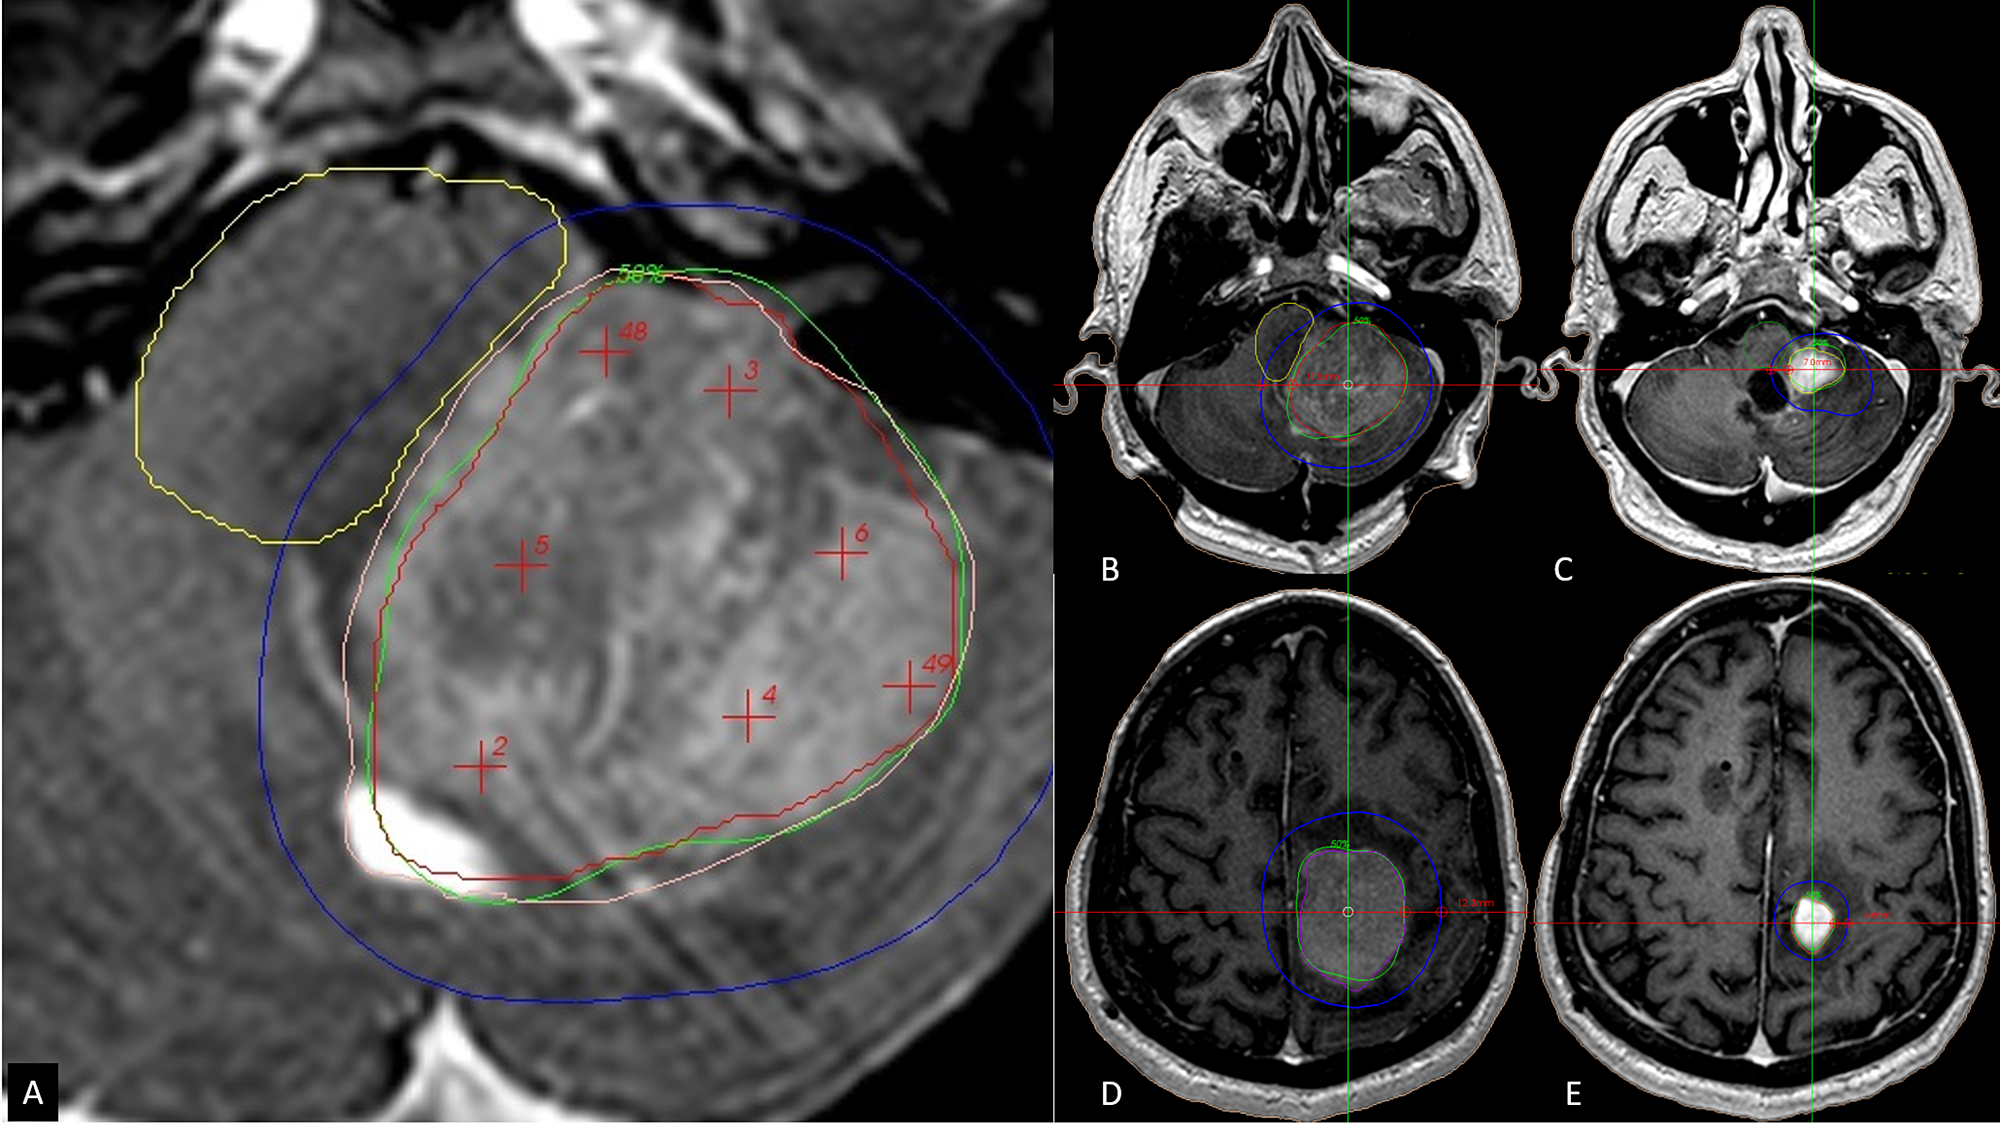

From www.cureus.com

Cureus TwoSession Radiosurgery for Large Primary Tumors Affecting Radiosurgery Brain Tumor Side Effects Skin irritation at treatment site; For instance, if you are. side effects can depend on which area of the brain has been treated and the dose of radiation given. Stereotactic radiosurgery, such as gamma knife, is often used to treat noncancerous (benign) and cancerous (malignant). side effects of radiosurgery are often related to sending high doses of radiation. Radiosurgery Brain Tumor Side Effects.